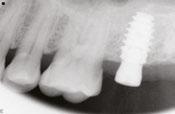

Figure 1: The patient’s panoramic radiograph upon initial consultation

molars in January 2019. The past medical history was significant for cystic fibrosis and depression. He had an allergy to sulfa medications and was taking the following medications: Pulmozyme® (dornase alpha), testosterone, prednisone, and nifedipine. The patient presented with a chief complaint of “I didn’t think I was going to live this long with cystic fibrosis, but I did, and now I am ready to take care of my needs.” The clinical examination was significant for a grossly carious dentition in need of repair (Figure 1). After reviewing several options, it was decided to extract the non-restorable left maxillary first, second, and third molars and to restore the maxillary left first and second molars with fixed implant-retained restorations. With potential healing concerns secondary to his cystic fibrosis, the addition of platelet-rich fibrin (PRF) was discussed. The patient was taken to the surgical operatory where the blood pressure was taken, a pulse oximeter placed, and an IV was started using a 21-gauge butterfly catheter in the right antecubital fossa. PRF protocol was followed using Intraspin® centrifuge (BioHorizons; Birmingham, Alabama), and anesthesia was maintained thereafter using a balance technique. Maxillary left first, second, and third molars were surgically removed, and the resulting extraction sockets were curetted free of granulation tissue. PRF clots and membranes were prepared as described by Choukroun, et al.15 The PRF was mixed 50/50 with MinerOss® mineralized allograft cancellous bone particles (BioHorizons; Birmingham, Alabama) resulting in a “sticky bone preparation” that was placed in the maxillary left first and second molar sockets (Figure 2). Two PRF membranes were placed across the extraction sites (Figure 3), and 3-0 PTFE interrupted sutures were placed affording good wound apposition (Figure 4). Adequate soft tissue healing was observed at a 3-week postoperative check.

Figure 7: Postoperative periapical radiograph immediately after implant placement Figure 8: Notice the lack of bone density in the ungrafted maxillary left third molar socket Figure 9: The PRF/cortical cancellous bone graft increased the density of the implant site as seen in the postoperative transaxial CBCT view